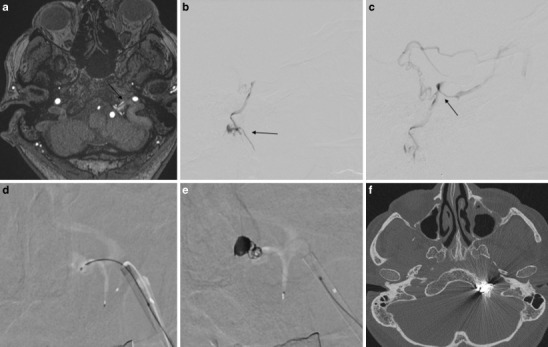

Fig. 5.

Case #3: a MR angiography source image from three-dimensional time-of-flight shows abnormal vascularization in the right hypoglossal canal compatible with a DAVF of the anterior condylar vein. b Anteroposterior (AP) view after injection of the left ascending pharyngeal artery shows a DAVF of the anterior condylar vein with a venous pouch located medially to the jugular bulb. c AP view after injection of the left ascending pharyngeal artery shows the microcatheter in the venous pouch and partial coil occlusion of the DAVF due to a transvenous approach. d AP view shows the complete occlusion of the DAVF; e MR angiography source image from three-dimensional time-of-flight shows no abnormal vascularization in the right hypoglossal canal anymore. f Axial computed tomography (CT) scan of the skull base shows the location of the coils in the right hypoglossal canal

The transvenous intervention was carried out through a transfemoral approach. A 6Fr guide catheter was tracked into the right internal jugular vein. A microcatheter was advanced to the point of the fistula at the ACV and 11 detachable coils were deployed in the ACV und ACC (Fig. 5c, d).

The post-interventional MRI scan confirmed the complete occlusion of the DAVF (Fig. 5e). A computed tomography (CT) scan of the skull base confirmed the location of the coils in the HC (Fig. 5f). The tinnitus disappeared immediately after the second treatment and the patient was discharged 3 days after the treatment.